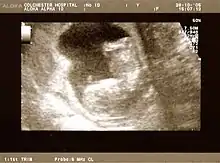

The result of an ultrasonography: a black and white image that shows a clear view of the interior abdomen

A dating scan at 12 weeks

Obstetric ultrasonography is routinely used for dating the gestational age of a pregnancy from the size of the fetus, determine the number of fetuses and placentae, evaluate for an ectopic pregnancy and first trimester bleeding, the most accurate dating being in first trimester before the growth of the foetus has been significantly influenced by other factors.[22] Ultrasound is also used for detecting congenital anomalies (or other foetal anomalies) and determining the biophysical profiles (BPP), which are generally easier to detect in the second trimester when the foetal structures are larger and more developed.[23]

X-rays and computerized tomography (CT) are not used, especially in the first trimester, due to the ionizing radiation, which has teratogenic effects on the foetus.[24] No effects of magnetic resonance imaging (MRI) on the foetus have been demonstrated,[25] but this technique is too expensive for routine observation. Instead, obstetric ultrasonography is the imaging method of choice in the first trimester and throughout the pregnancy, because it emits no radiation, is portable, and allows for realtime imaging.[26]

The safety of frequent ultrasound scanning has not been confirmed. Despite this, increasing numbers of women are choosing to have additional scans for no medical purpose, such as gender scans, 3D and 4D scans.[27] A normal gestation would reveal a gestational sac, yolk sac, and fetal pole.[28]

The gestational age can be assessed by evaluating the mean gestational sac diameter (MGD) before week 6, and the crown-rump length after week 6. Multiple gestation is evaluated by the number of placentae and amniotic sacs present.[29]